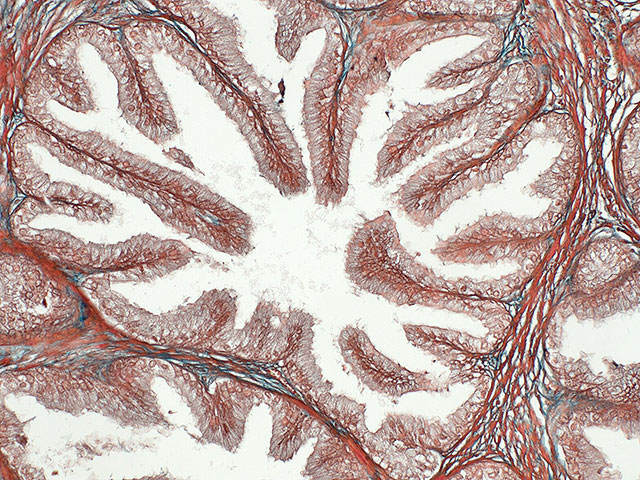

Wikipedia.org. Фото: Endolysosome